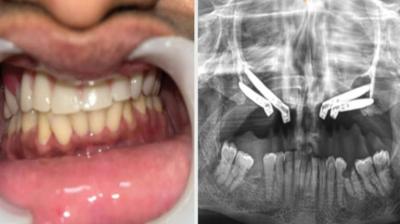

24 वर्षीय युवती के चेहरे पर लौटी मुस्कान और आत्मविश्वास

6 Sep, 2025 10:00 PM IST | SAMACHARPRADESH.COM

एम्म में जटिल सर्जरी को सफलतापूर्वक अंजाम दिया है। इस सर्जरी में ट्यूमर के कारण काटे गए निचले जबड़े को पैर की हड्डी से दोबारा बनाया गया और उसमें 13...